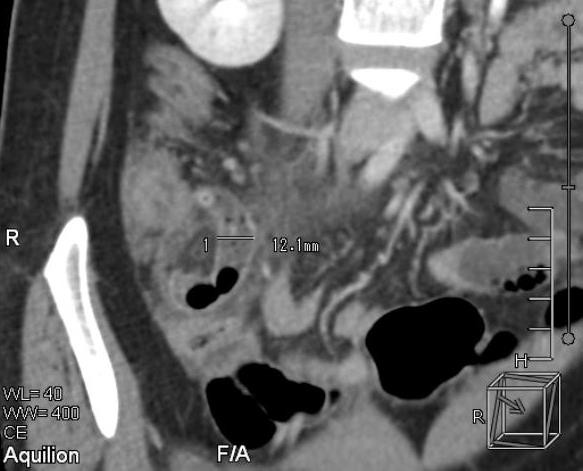

Ảnh chụp vị trí viêm ruột thừa cấp của nữ bệnh nhân.